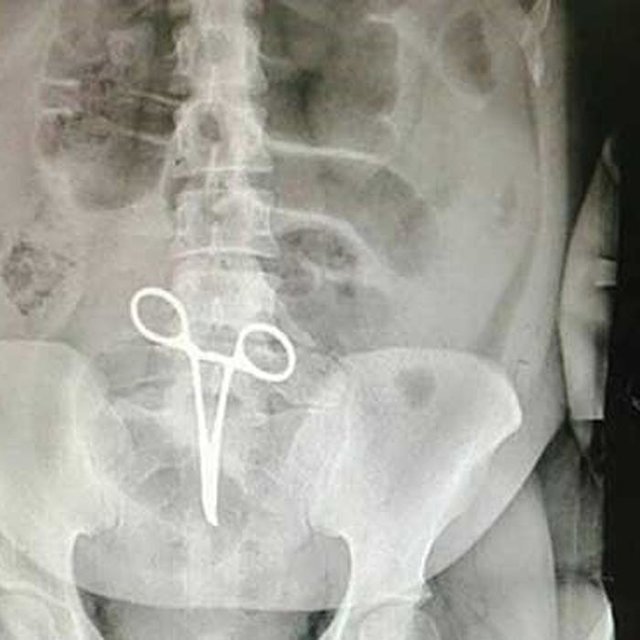

عذرخواهی رییس بیمارستان به دلیل جا ماندن قیچی در شکم بیمار

رئیس بیمارستان شهید بهشتی اردستان گفت: اشتباهی که در بیمارستان اردستان اتفاق افتاده است یکی از موارد نادر پزشکی است که متأسفانه رسانه‌ای شد.

محمدحسین مقامی در گفت‌وگو با ایسنا، اظهار کرد: این بیمار قبل از این اتفاق دو بار به دلیل پارگی روده و رعایت نکردن توصیه‌های پزشکی عمل جراحی داشت که متأسفانه در عمل سوم با توجه به رعایت نکردن توصیه‌های پزشکی دچار درد در ناحیه شکم می‌شود و به بیمارستان مراجعه می‌کند.

وی بابیان اینکه اشتباه رخ داده یکی از موارد نادر پزشکی بود که تاکنون در این بیمارستان اتفاق نیفتاده بود، افزود: بعد از اینکه عکس از ناحیه  شکم  بیمار گرفته می‌شود همکاران متوجه جسم خارجی(پنس) در داخل شکم بیمار می‌شوند.

رئیس بیمارستان شهید بهشتی اردستان، ادامه داد: بدون هیچ فوت وقتی مقدمات عمل جراحی سوم انجام می‌شود و عمل جراحی و عملیات بیرون آوردن پنس توسط پزشک جراح که این بیمار را عمل کرد انجام می‌شود.

مقامی گفت: این اشتباه پزشکی در بیمارستان‌های دیگر کشور هم رخ می‌دهد اما در بیمارستان‌های دیگر رسانه‌ای نمی‌شود.

وی با اشاره به اینکه اتفاقی که در بیمارستان اردستان افتاده نه تخلف بود نه  قصور، افزود: اتفاقی که در بیمارستان اردستان رخ داد یک کوتاهی بوده است. کاری که باید در اتاق عمل انجام می‌شد این بود که قبل و بعد عمل سِت پزشکی باید شمارش می‌شد.

رئیس بیمارستان شهید بهشتی اردستان در جواب سؤال خبرنگار ایسنا مبنی بر اینکه پنس داخل شکم بیمار آیا باعث ضربه زدن به ناحیه داخل شکم بیمار هم شده است، افزود: باید توجه داشته باشیم که این‌گونه اتفاقات هیچ آسیبی به بیمار نمی‌رساند. متأسفانه خبرهایی که به اشتباه درباره این موضوع انتشار پیدا کرد یک دروغ رسانه‌ای بود. البته بابت این اتفاق از مردم عذرخواهی می‌کنیم.

مقامی افزود: این اطمینان را به مردم اردستان می‌دهیم که دیگر شاهد این‌گونه اتفاقات نباشند.